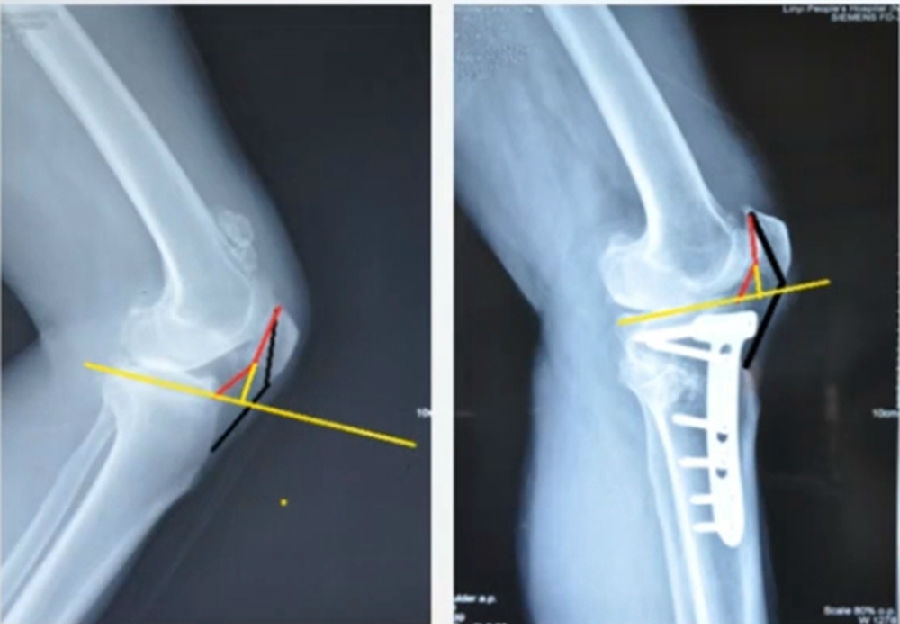

OWHTO上行截骨与下行截骨

3)下行性OWHTO对髌骨高度影响较小。

4)术前存在低位髌骨、髌股关节炎或内翻矫正度数较大时可考虑下行性OWHTO

有文献证实下行截骨对髌骨的高度确实没有明显影响。

OWHTO下行截骨对髌骨的影响

第一次为该患者做了传统上行开放截骨,撑开角度较大,术后用三种方法测量髌骨高度,发现髌骨高度受到影响,髌骨变低了。

左膝上行OWHTO(初次)

上行OWHTO髌骨高度测量

ISI法测量髌骨无明显变化;CDIBPI法测量髌骨降低明显;患者屈膝锻炼困难。

第二次来院做另一侧肢体时,采用下行截骨,术后患者髌骨高度,无论用哪种方法测量都无明显变化,而且患者膝关节功能迅速得到恢复。

右膝下行OWHTO(再次)

下行OWHTO髌骨高度测量

ISI法测量髌骨无明显变化;CDIBPI法测量髌骨无明显变化;患者屈膝明显改善。